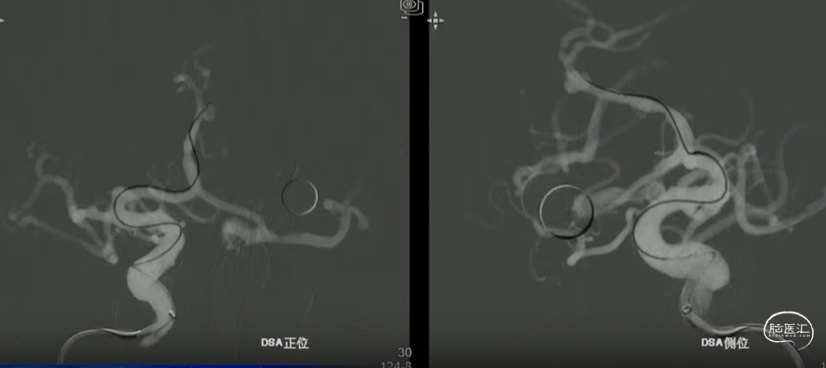

术后即刻造影,动脉瘤滞留明显,载瘤动脉管腔通畅无狭窄,支架贴壁理想。

“如意”血流导向密网支架很好打开,镍钛小球助力支架更好的二次打开,支架释放中就能达到自膨打开,无需按摩,是一款各方面性能都不错的支架。

本例病例奇大脑前A3段动脉瘤,从大脑前动脉瘤起始段有广泛伴有动脉粥样硬化的斑块,血管路径过于迂曲,且颅内支撑导管的位置过低,仅位于C4段,无法提供很好的支撑性和力的传导功能,这样的情况会导致支架推送性能会有下降,释放中会降低可控性,对于这样的病例,颅内支撑导管上到更高,上至颈内动脉瘤末端或A1段会起到更好的帮助。